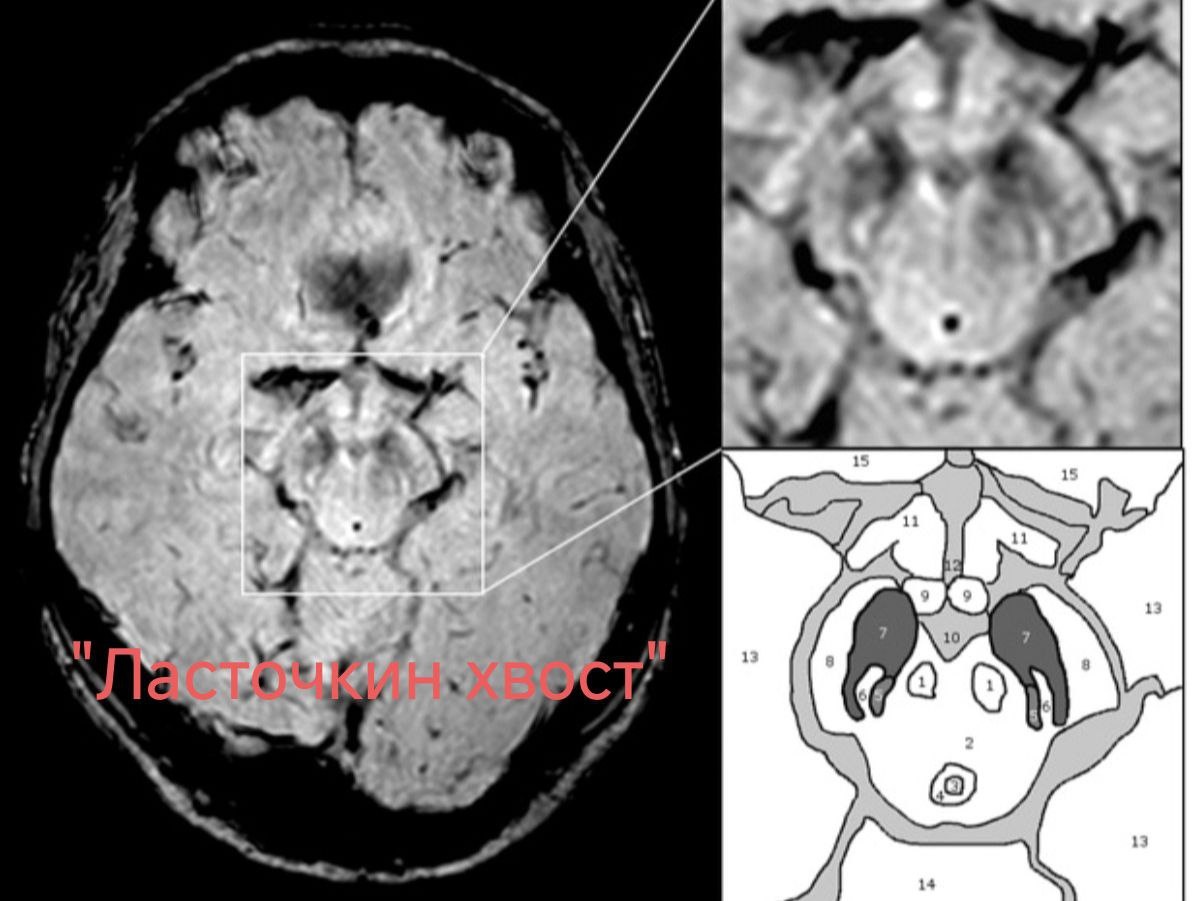

🖥 Нигросома-1, расположенная в задней трети чёрной субстанции, имеет высокий МР-сигнал на SWI в аксиальной плоскости в форме запятой или запятой с отростком. В сочетании с низкой интенсивностью МР-сигнала по SWI спереди, сбоку и медиально, имеется сходство с характерным раздвоенным хвостом ласточки.

При болезни Паркинсона происходит потеря нигросомы-1, и на этом основании отсутствие симптома «ласточкин хвост» может быть полезным МР-признаком, специфичным для этого заболевания.